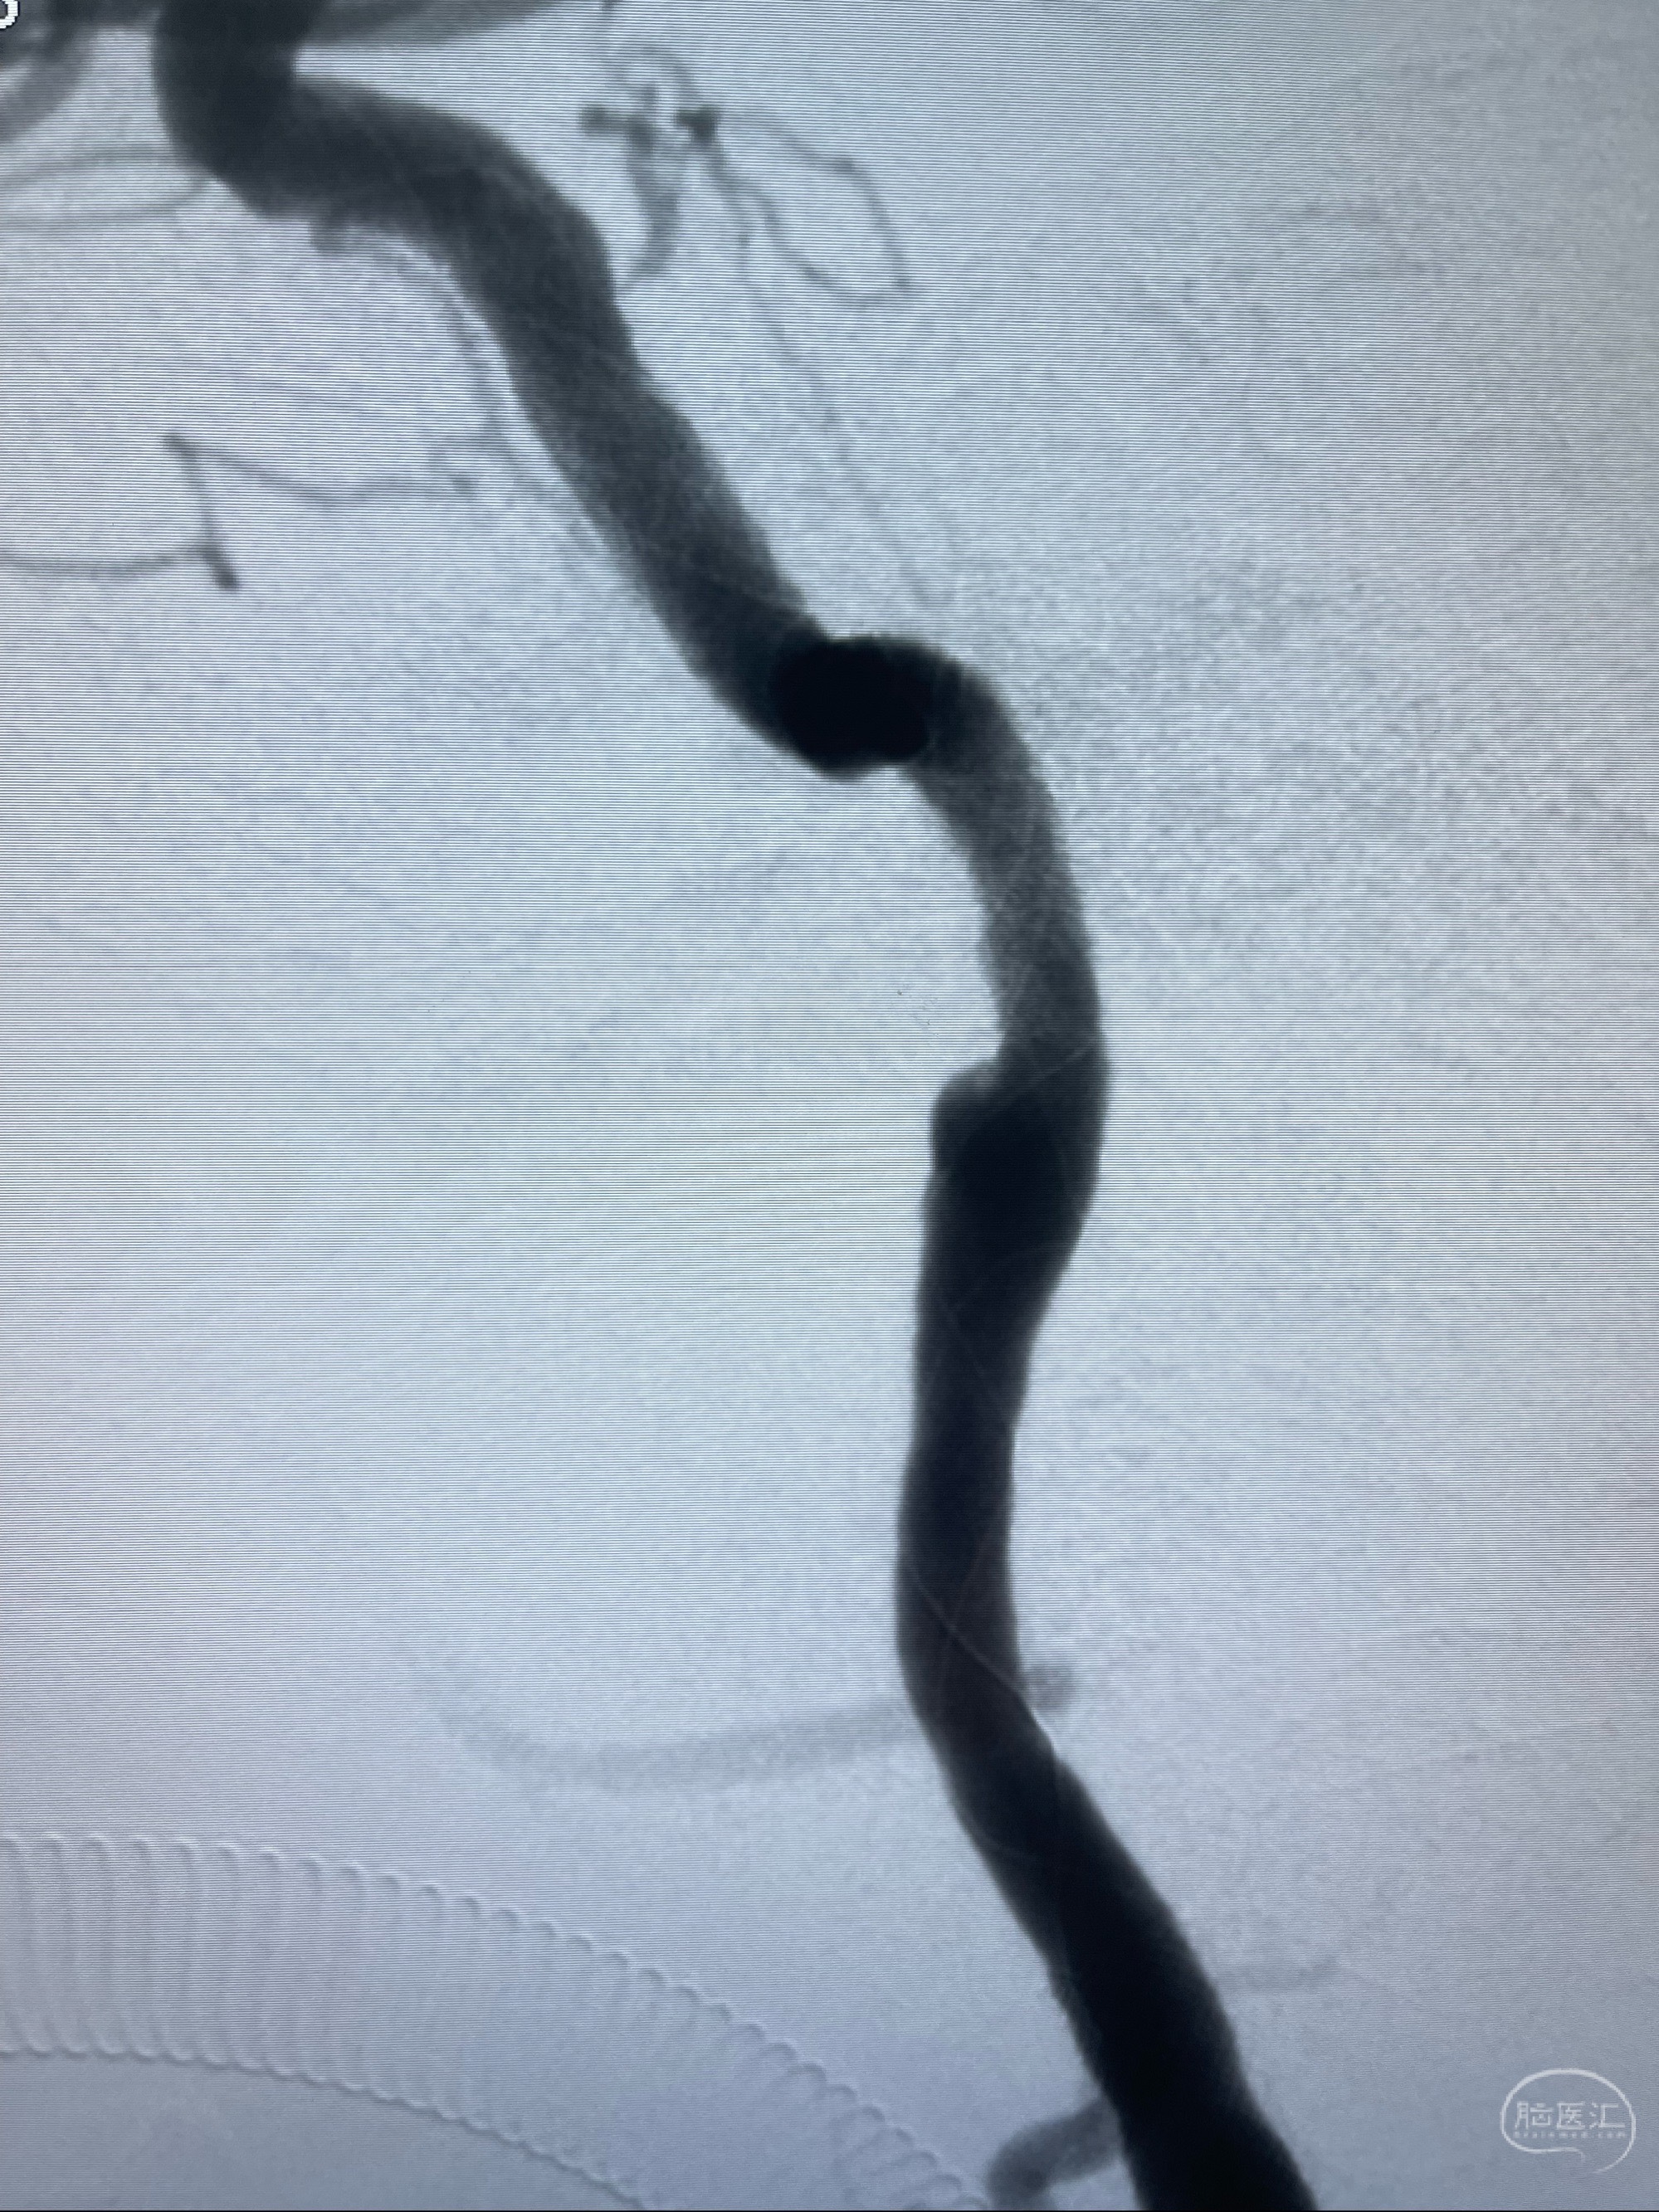

2023-07-10DSA:右侧颈内动脉岩骨段夹层伴中偏重度狭窄改变,左侧颈总动脉闭塞、右侧颈外动脉由右侧肋颈干甲颈干吻合代偿

箭头所示为颈内动脉岩骨段重度狭窄,结合MRI,考虑为肿瘤侵犯右侧颈内动脉

箭头以近至支架段管腔不规则狭窄